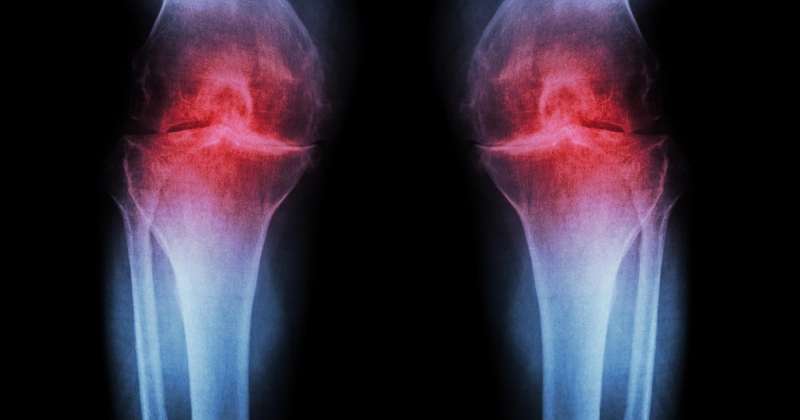

حقنة مضادة للشيخوخة تعيد نمو غضروف الركبة

أعلن باحثون في جامعة ستانفورد الأميركية عن ابتكار علاج ثوري يستعيد الغضروف الذي يتآكل بشكل طبيعي في ركب الفئران المسنة، وفقاً لدراسة نُشرت في مجلة «ساينس» العلمية.ويعمل العلاج القا...